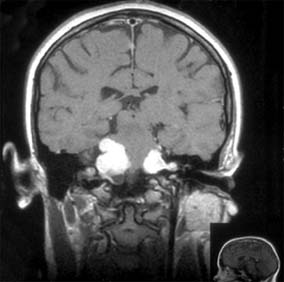

Neurofibromatosis is a generalized hereditary disease characterized by multiple tumors of the skin, central nervous system, peripheral nerves, and nerve sheaths. Other developmental anomalies, particularly of the bones, may be associated. There are two distinct dominant conditions. Neurofibromatosis 1 (peripheral) (Recklinghausen's disease) consists of multiple café au lait spots (99%), peripheral neurofibromas, and Lisch nodules (iris hamartomas) (93%), and its gene lies on the pericentromeric region of chromosome 17. The frequency is 1:3000 live births, with 100% penetrance. In neurofibromatosis 2 (central), there may be few or no café au lait spots or peripheral neurofibromas, but bilateral acoustic neuromas (vestibular schwannomas) are present (Figure 14-34) and its gene lies on chromosome 22. The frequency is 1:35,000. Neurofibromatosis 1 is associated with tumors primarily of astrocytes and neurons, whereas neurofibromatosis 2 is associated with tumors of the meninges and Schwann cells. There is no racial predominance. Signs may be present at birth but are activated during pregnancy, during puberty, and at menopause.

Figure 14-34: Coronal MRI of bilateral acoustic neuromas in neurofibromatosis 2.